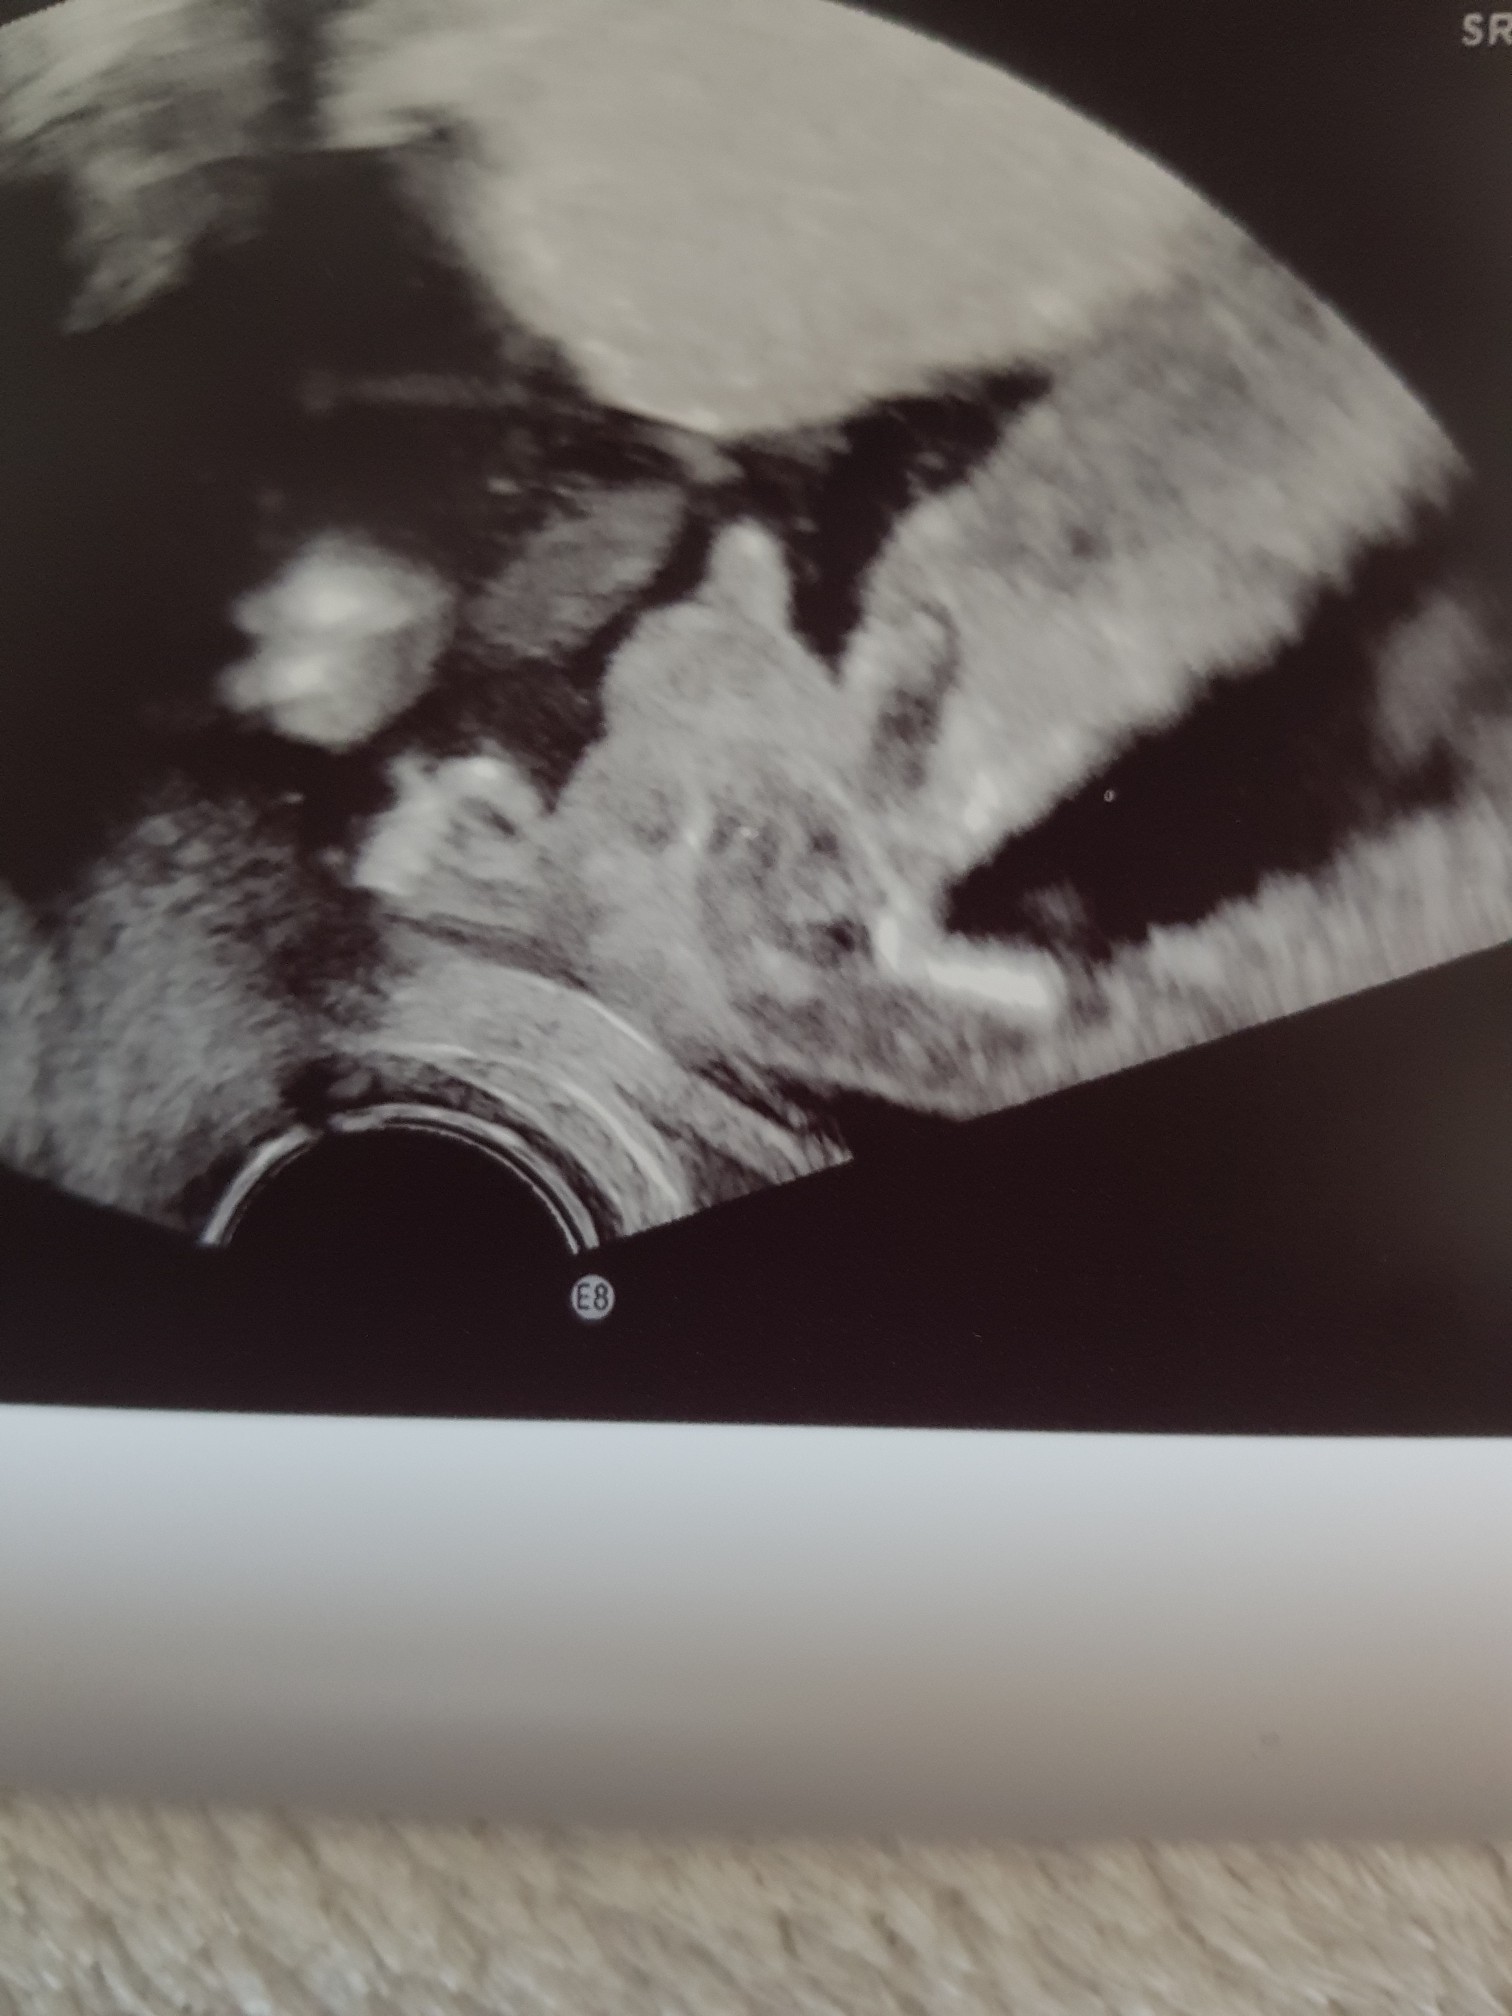

Melduję że my już dzisiaj po wizyciePotwierdziło się z prenatalnych że będzie dziewczynka

Pokazywał mi jej wargi sromowe ale ja oczywiście nic tam nie widziałam hehe Ogólnie Liliana (myślę że to imię już zostanie) bardzo szybko rośnie, termin porodu zmienił mi się z 18 lipca na 13 więc chyba będzie duża po tatusiu

Mózg się ładnie prawidłowo dzieli, serce pięknie bije, są wszystkie paluszki, można więc w spokoju czekać miesiąc na połówkowe